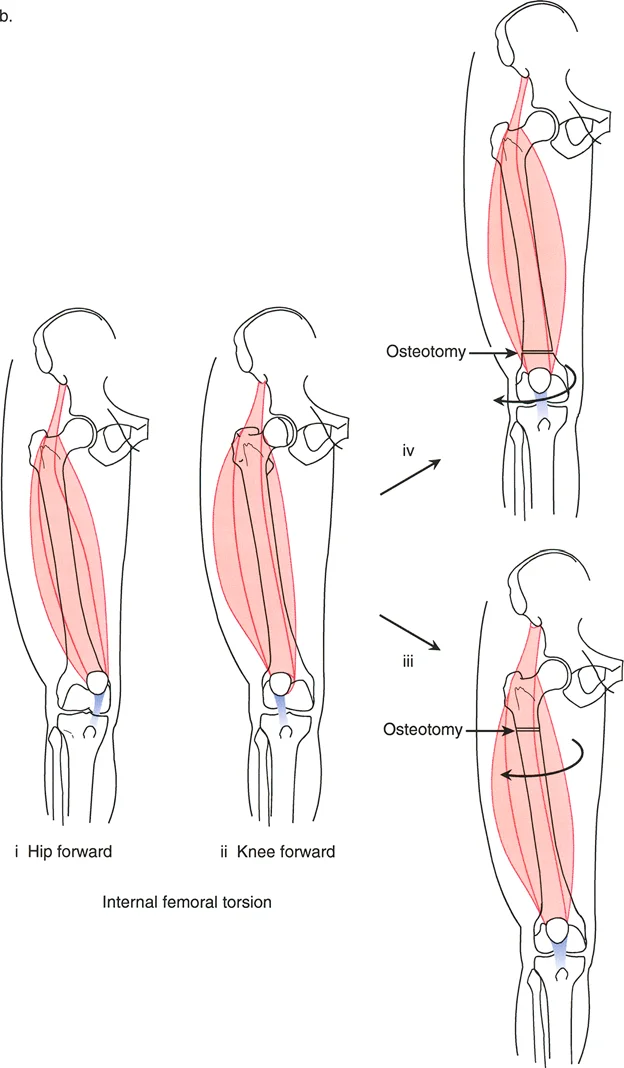

أهمية التصحيح ثلاثي الأبعاد

عندما يكون العظم مشوهاً في كل من الانحراف الزاوي والدوران، فإن أي محاولة لتصحيح أحد الجانبين دون الآخر قد تؤدي إلى نتائج عكسية أو حتى مضاعفات خطيرة. على سبيل المثال:

* إذا قمت بتصحيح الانحناء فقط وتجاهلت الدوران، فقد يظل المريض يعاني من مشكلة في المشي أو ألم في الركبة.

* إذا تم تصحيح الدوران بشكل خاطئ أو في مستوى غير صحيح، فقد يؤثر ذلك على عمل العضلات المحيطة، خاصة عضلات الفخذ الأمامية (الرباعية)، مما قد يؤدي إلى خلع صابونة الركبة أو تآكل غضروف الركبة (تلين الغضاريف).

* يمكن أن يؤدي التصحيح غير الدقيق أيضاً إلى شد غير طبيعي على الأعصاب والأوعية الدموية، مما قد يسبب تلفاً عصبياً مثل شلل العصب الشظوي، وهو ما يؤثر على القدرة على رفع القدم.

لهذا السبب، يركز الأستاذ الدكتور محمد هطيف على التخطيط الجراحي ثلاثي الأبعاد الذي يأخذ في الاعتبار كل زاوية وكل محور، لضمان تصحيح شامل ودقيق يحقق أفضل النتائج الوظيفية ويحافظ على سلامة المريض.

* زيادة النسخة الأمامية للفخذ (Increased Femoral Anteversion): تعني أن رأس عظم الفخذ يدور للأمام أكثر من اللازم، مما يجعل الطفل يمشي وقدماه تتجهان للداخل (intoeing gait).

تحديد مستوى التشوه بدقة

إن تحديد المستوى الدقيق للتشوه الدوراني هو أحد أهم الخطوات في التخطيط الجراحي. على الرغم من أن الدوران هو تشوه زاوي في المستوى المستعرض، إلا أن موقعه على طول العظم (قريب من المفصل أو بعيد عنه) يؤثر بشكل كبير على كيفية تصحيحه وتأثيره على الأنسجة المحيطة.

- في حالات ما بعد الإصابة: يكون مستوى التشوه واضحاً عادة عند موقع الكسر الملتئم.

- في الحالات الخلقية أو التنموية: يتطلب تحديد مستوى التشوه استنتاجاً سريرياً دقيقاً يعتمد على تأثيره العميق على مسار العضلات والأوتار. يعتمد الدكتور هطيف على خبرته الواسعة في تقييم هذه الحالات لتحديد المستوى الأمثل لقطع العظم.